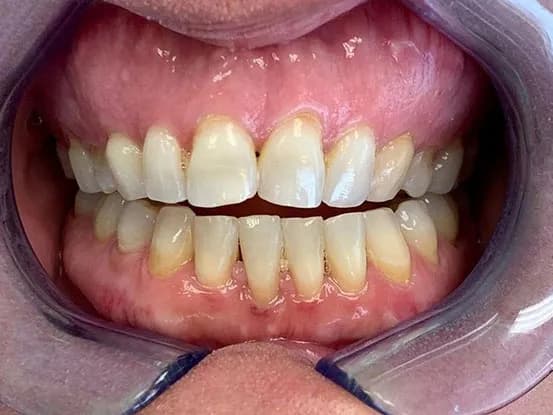

Case 11

62 year old female with overbite and multiple worned and discolored teeth and wanted a dental cosmetic makeover. 3 quadrants osseous surgery, crown lengthening and 20 units of E-Max restorations performed to restore smile to a more youthful look.